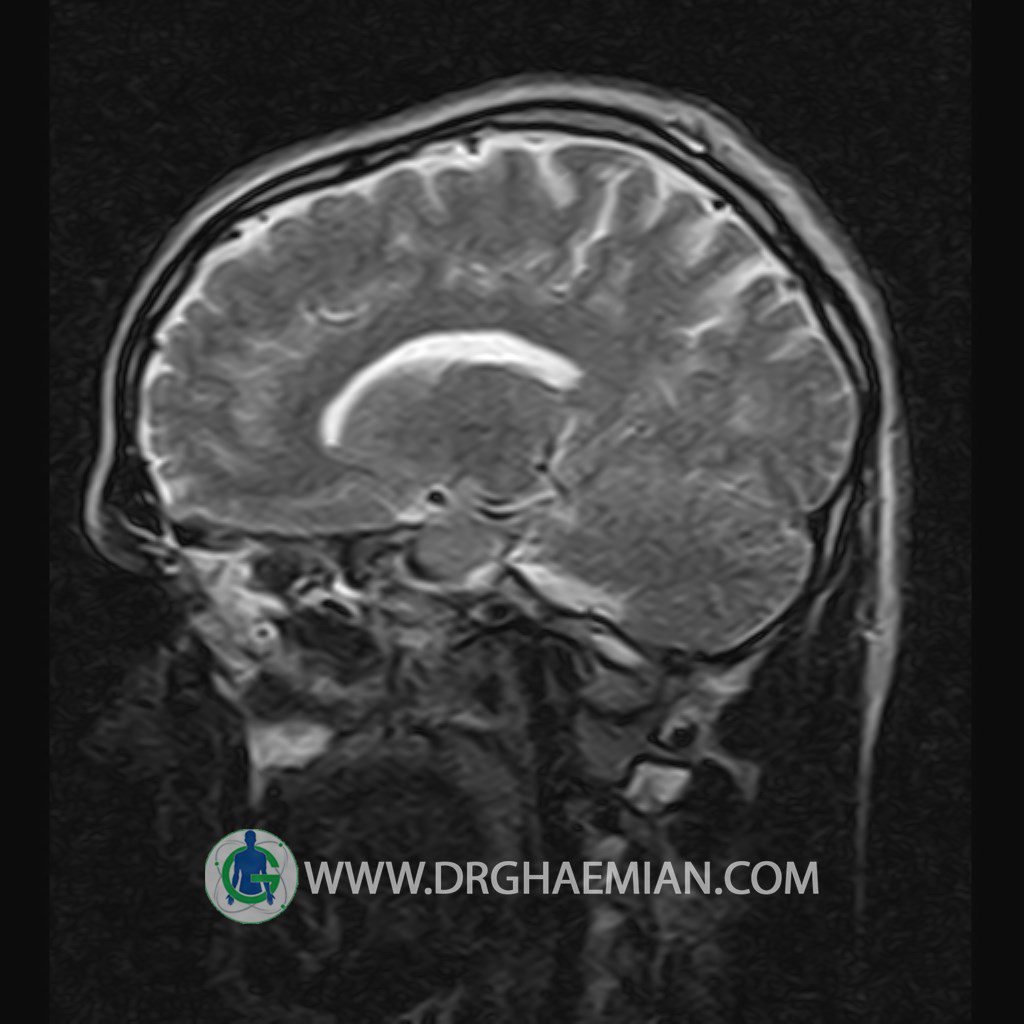

پزشکان اغلب از تصویربرداری ام آر آی برای تشخیص و درمان عارضه های پزشکی که فقط با استفاده از اشعه ایکس یا میدان مغناطیسی و امواج رادیویی قابل مشاهده است، استفاده می کنند. دستگاه ام آر آی تصاویر دقیق از ساختار های داخلی بدن ایجاد می کند. در این کیس یک میکروآدنوم در هیپوفیز بیمار مشاهده می شود.

HYPOPHYSIS MRI

(with and without contrast)

Technique: Axial , coronal T1 , Axial , coronal , sagittal T2 , Axial, coronal T1 post Gd & 64 dynamic thin coronal slices.

REPORT :

– Small hypoenhancing mass lesion ( 3 x 4 mm ) in posterior of pituitary stalk suggestive for micro adenoma

– Mucosal thickening in ethmoid & maxillary sinuses

is seen